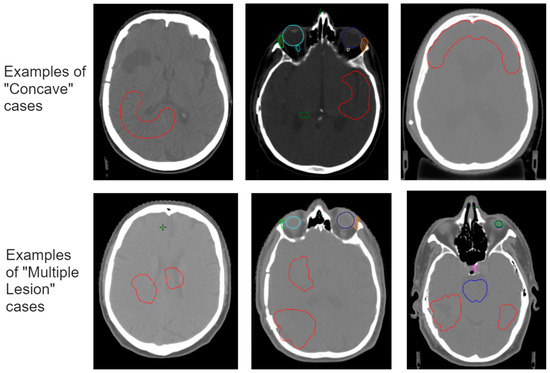

2.5. Improving the Model–Worst-Case Test Set

3.1. Results for Sensitivity

3.2. Improving the Model–Worst-Case Test Set